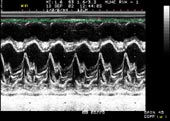

2D Echo

Two-dimensional echocardiography

can provide excellent images of the heart, Para cardiac

structures, and the great vessels. During a standard

echo, the sound waves are directed to the heart from

a small hand-held device called a transducer, which

sends and receives signals. Heart walls and valves

reflect part of the sound waves back to the transducer

to produce pictures of the heart. These images appear

in black and white and in color on a TV screen. They're

selectively recorded on videotape and special paper,

and later reviewed and interpreted by a cardiologist

(heart specialist).

From the pictures it is possible

to measure the size of each part of your heart, to

study motion and appearance of the valves and the

function of the heart muscle. Your physician uses

the measurements to determine how your heart is working

and whether or not any abnormalities are present.